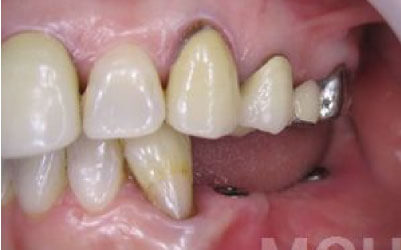

2 歯が傾いてくる、落ちてくる

歯は互いに支え合ってバランスを保っています。つまり、歯が抜けるとその支えがなくなり、抜けた部分の隣の歯が倒れたり、上の歯が下に沈んだりすることがあります。